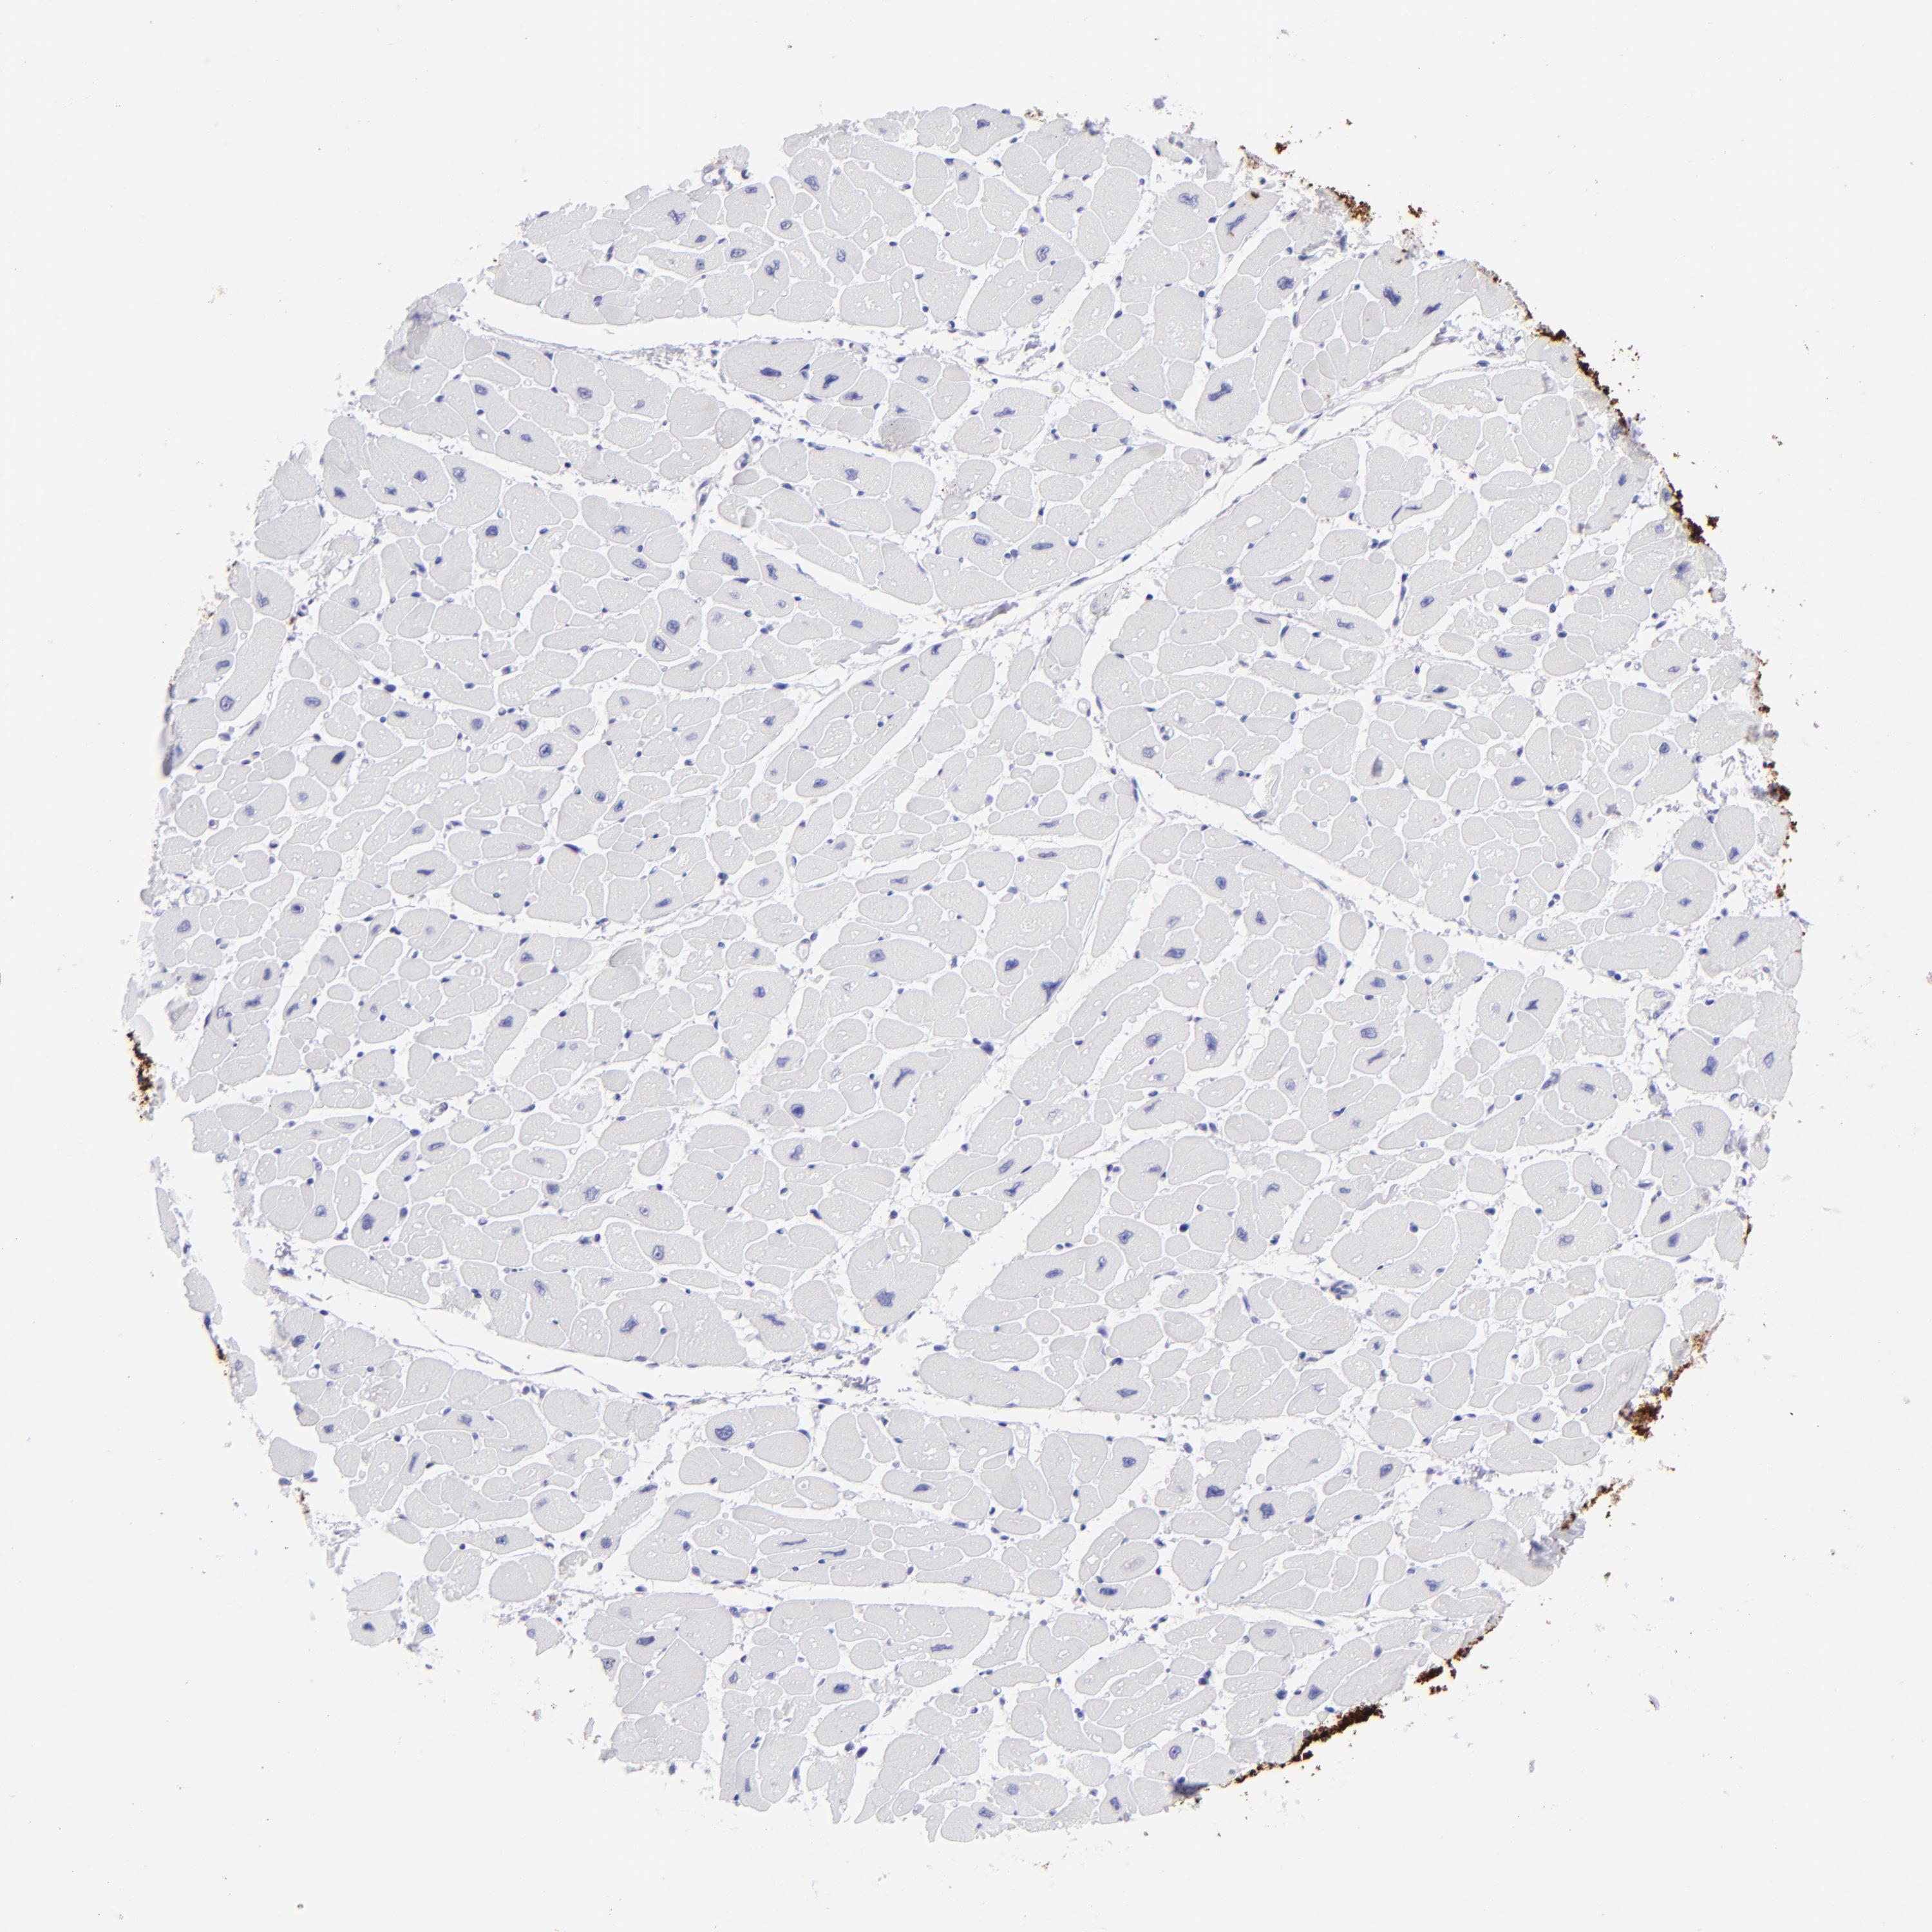

SLC1A3